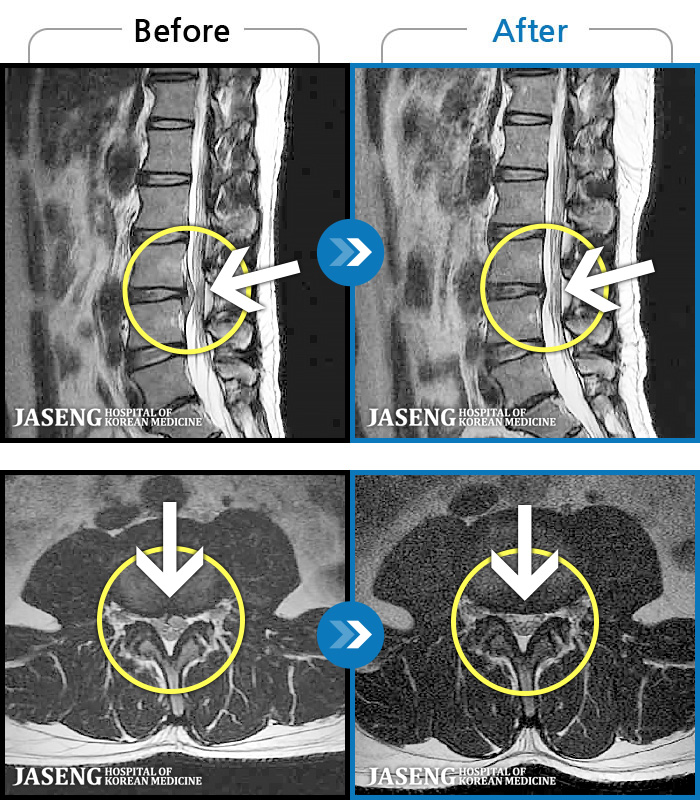

MRI ġ

119 MRI ũ ʸ Ȯϼ.

[Կñ:24.06.08~24.08.31]

[_㸮ũ] ġ ٸ ſ ؿ.

No.117

ȸ 553

2024.12.24